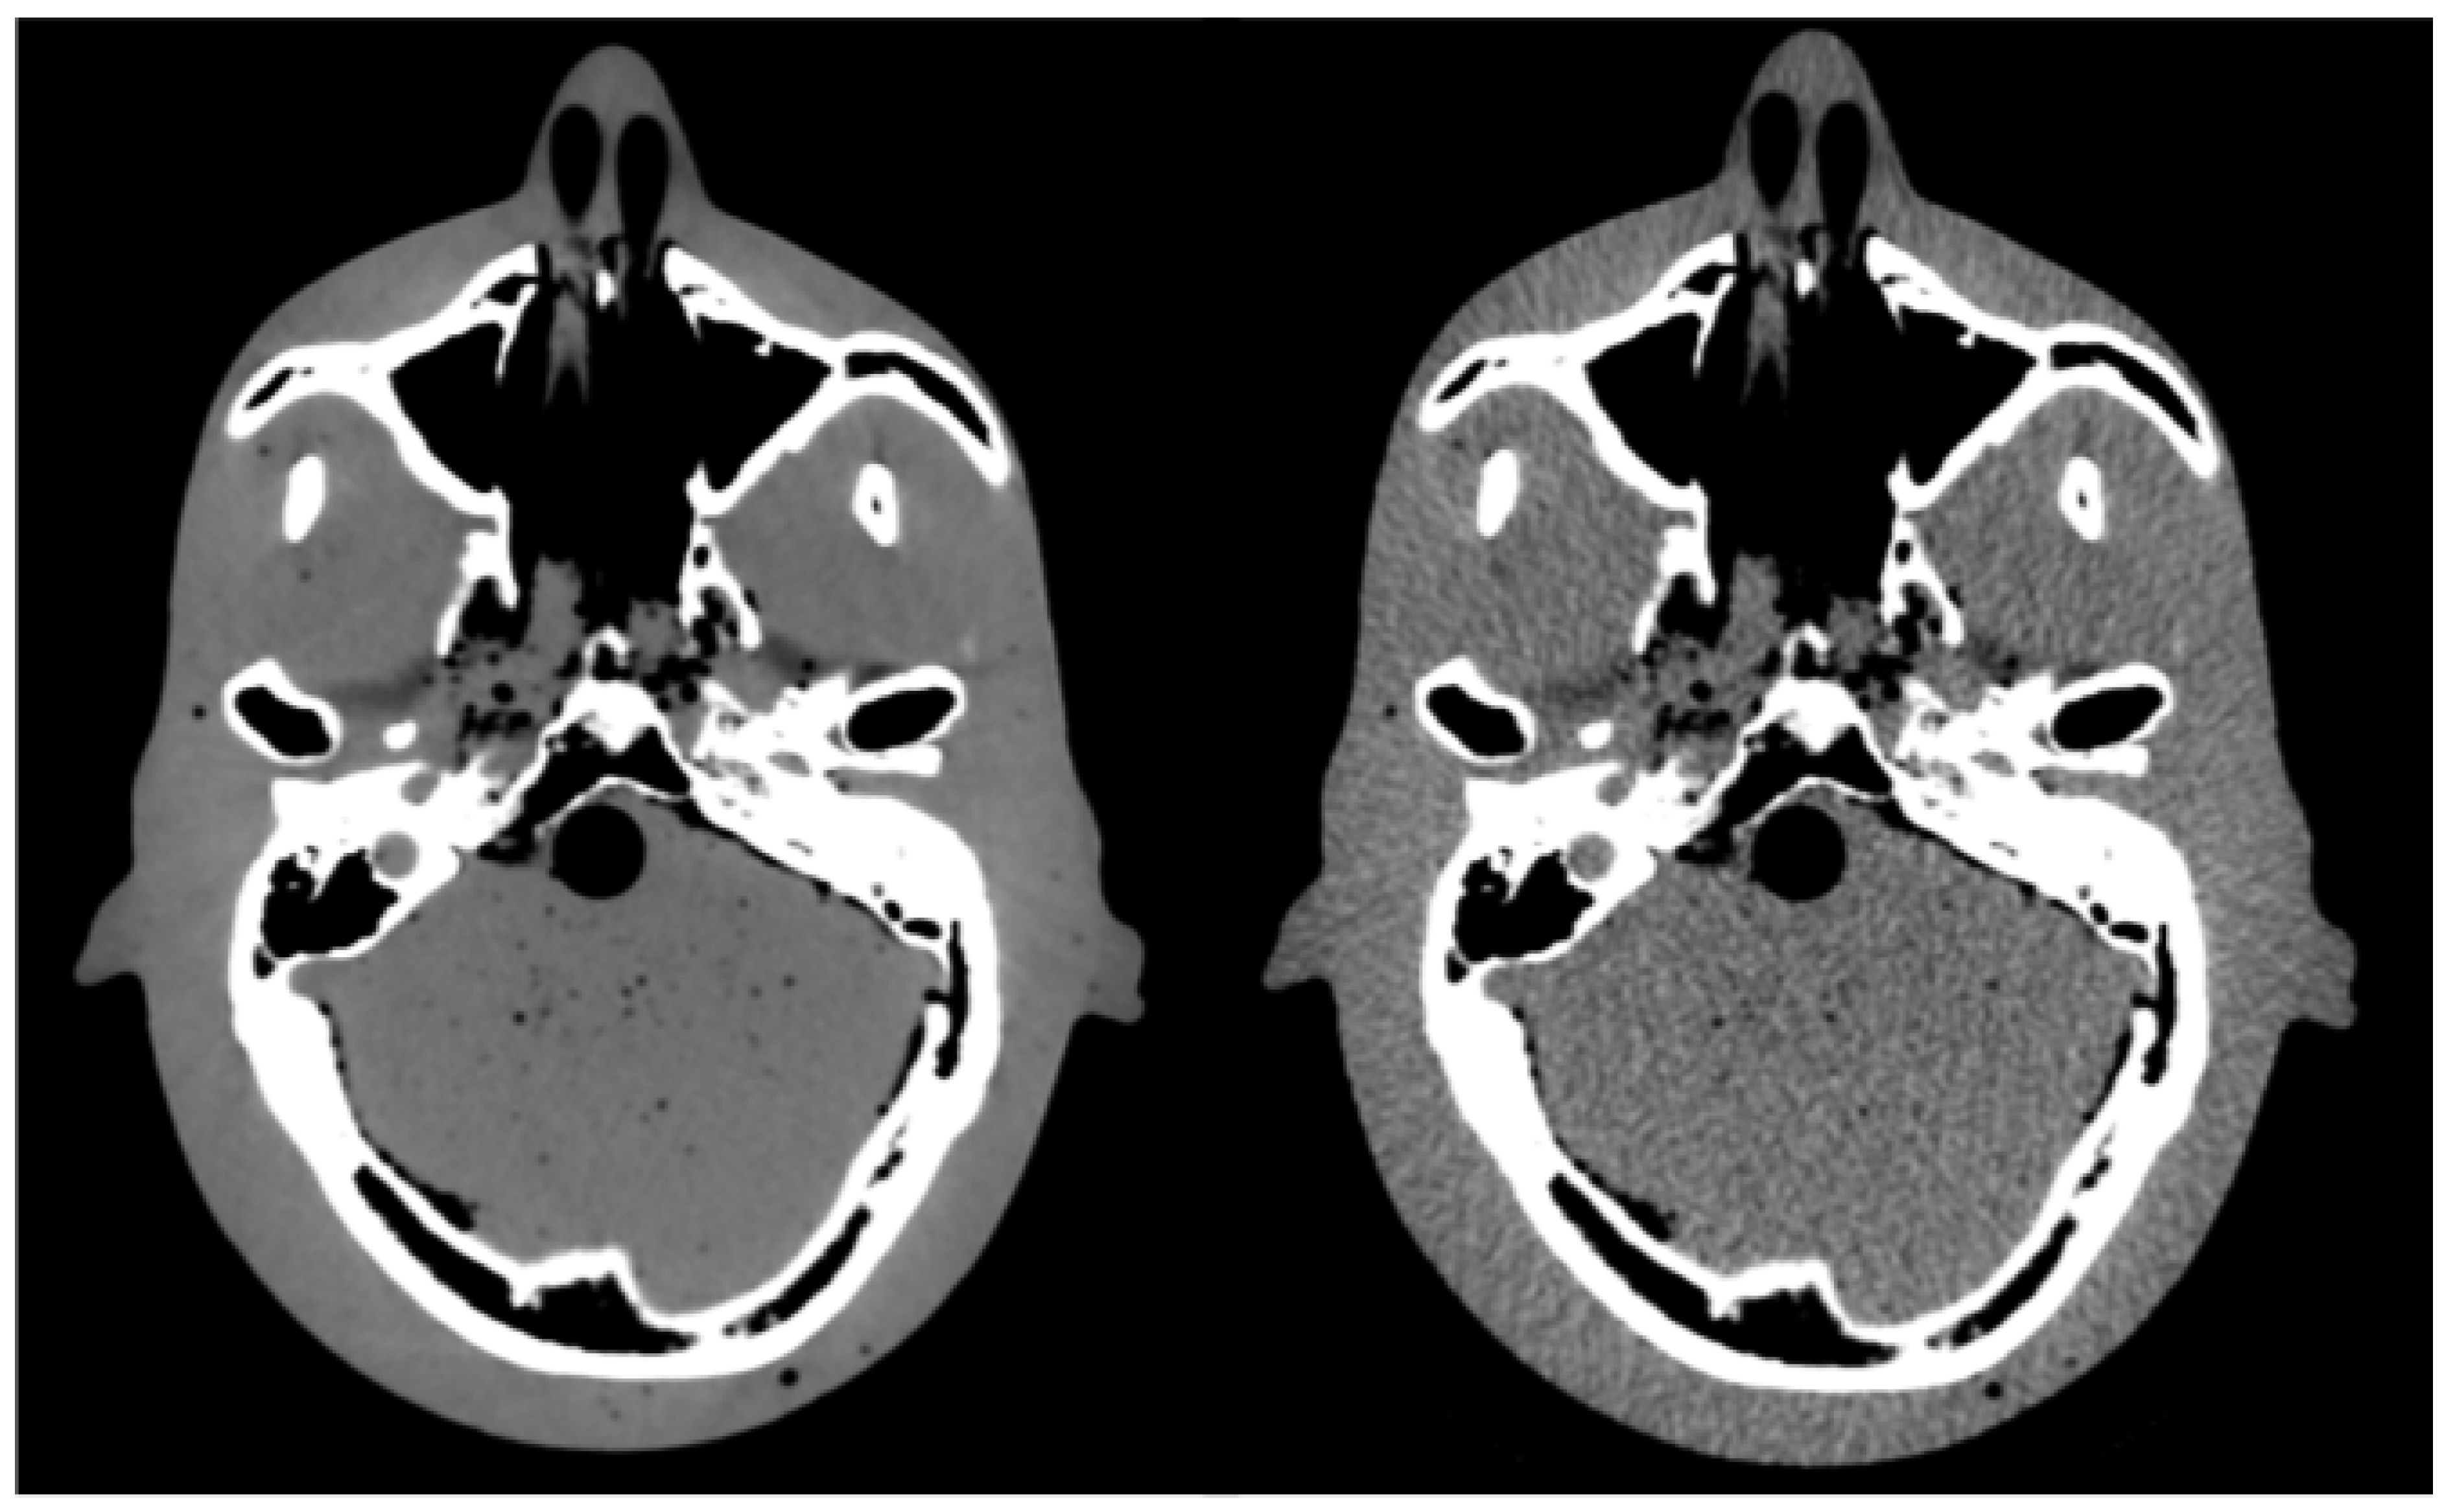

| Tube Current | CTDIvol | Tube Voltage | Pitch Factor | Slice Thickness |

|---|---|---|---|---|

| 400 mA (STD) | 166 mGy | 140 kV | 0.6 | 2.5 mm |

| 200 mA | 83 mGy | 140 kV | 0.6 | 2.5 mm |

| 100 mA | 41.5 mGy | 140 kV | 0.6 | 2.5 mm |

| 50 mA | 20.7 mGy | 140 kV | 0.6 | 2.5 mm |

| 25 mA | 10.4 mGy | 140 kV | 0.6 | 2.5 mm |

| 15 mA | 6.2 mGy | 140 kV | 0.6 | 2.5 mm |

| 10 mA | 4.2 mGy | 140 kV | 0.6 | 2.5 mm |